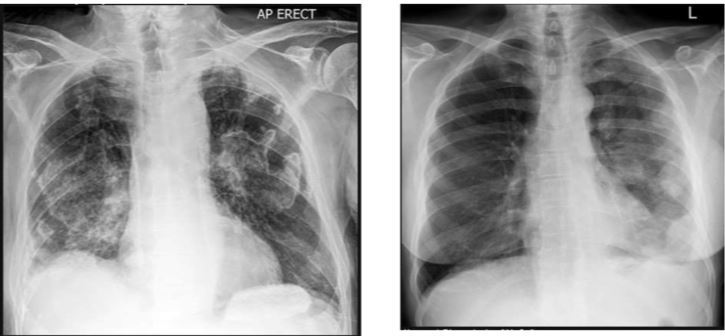

Describe the appearance of COVID on an X-ray?

Patchy opacification, bilateral, peripheral distribution and its more towards the base of the lungs.